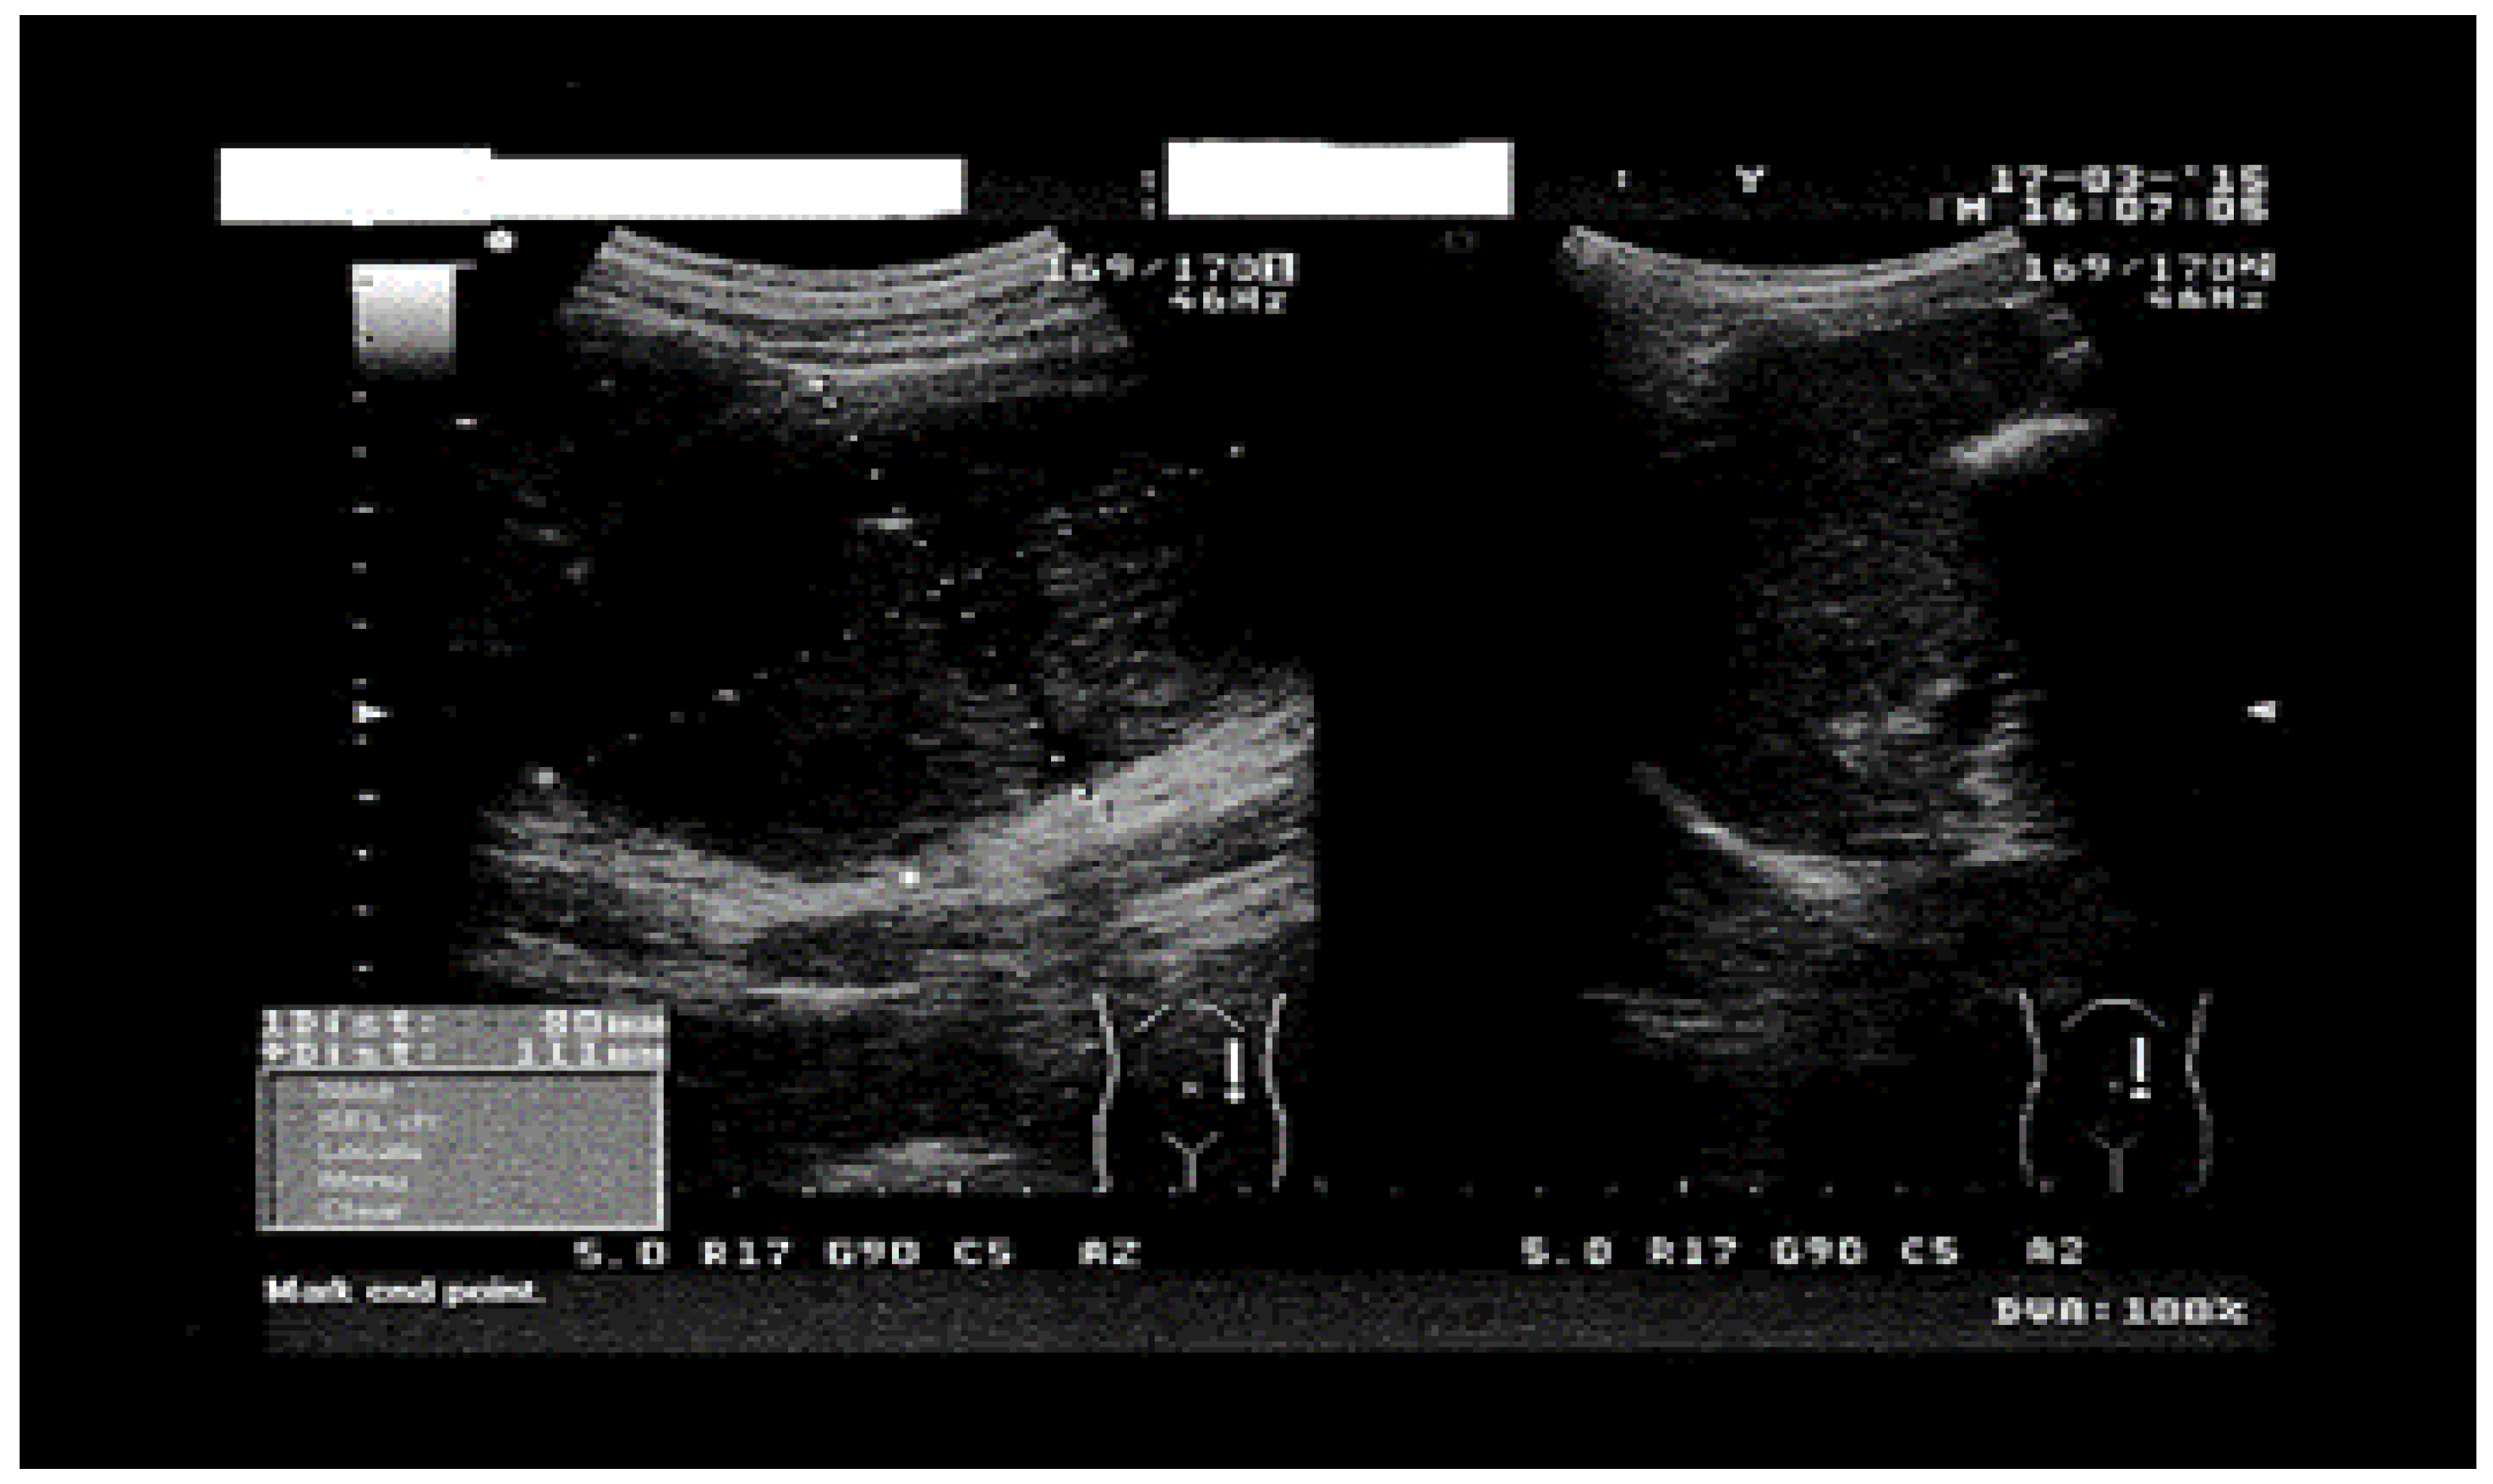

| 2020 | Yassine Merad [21] | Algeria | 16-year-old female, no pathological history | Right flank pain, a few episodes of vomiting in the previous 3 days | Positive | AUS CT | Pericystectomy + Albendazole 2 × 400 mg/day for 3 months |